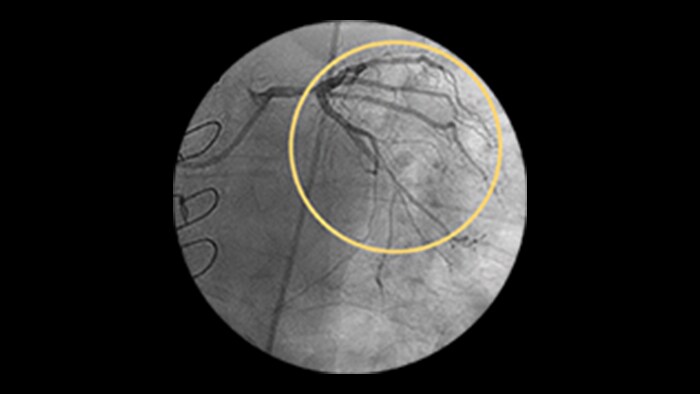

Calcified Lesions

An increasing number of patients with calcified coronary artery lesions are being referred for PCI. A recent pooled analysis reported moderate to severe target lesion calcification in 32% of patients.1